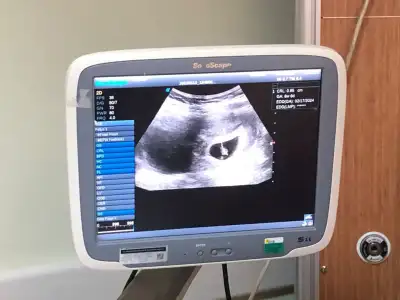

Ramiz teorisi kesede bebek sağ taraftaysa erkek sol taraftaysa kız ama karından bakılan ultrason resminde ayna gibi düşün canım sağ tarafta ise aslında sol oluyor kız solda ise sağ taraf oluyor erkekNasıl anlıyorsunuz anlamadım ben![]()

AnlamadimRamiz teorisi kesede bebek sağ taraftaysa erkek sol taraftaysa kız ama karından bakılan ultrason resminde ayna gibi düşün canım sağ tarafta ise aslında sol oluyor kız solda ise sağ taraf oluyor erkekbiraz karışık ama

Bebeğin yerleşim yerine göre teori

Şuna göre bakılıyor kız oluyor sanki seninki canım

Ben benimki ortada sanki![]()

Benimkine benziyor sağda yani kız oluyor galibaYa kızlar çok hoşsunuz dimi böyle ortaya kurulmuş ama ilk hali de var onu da ekleyeyim![]()